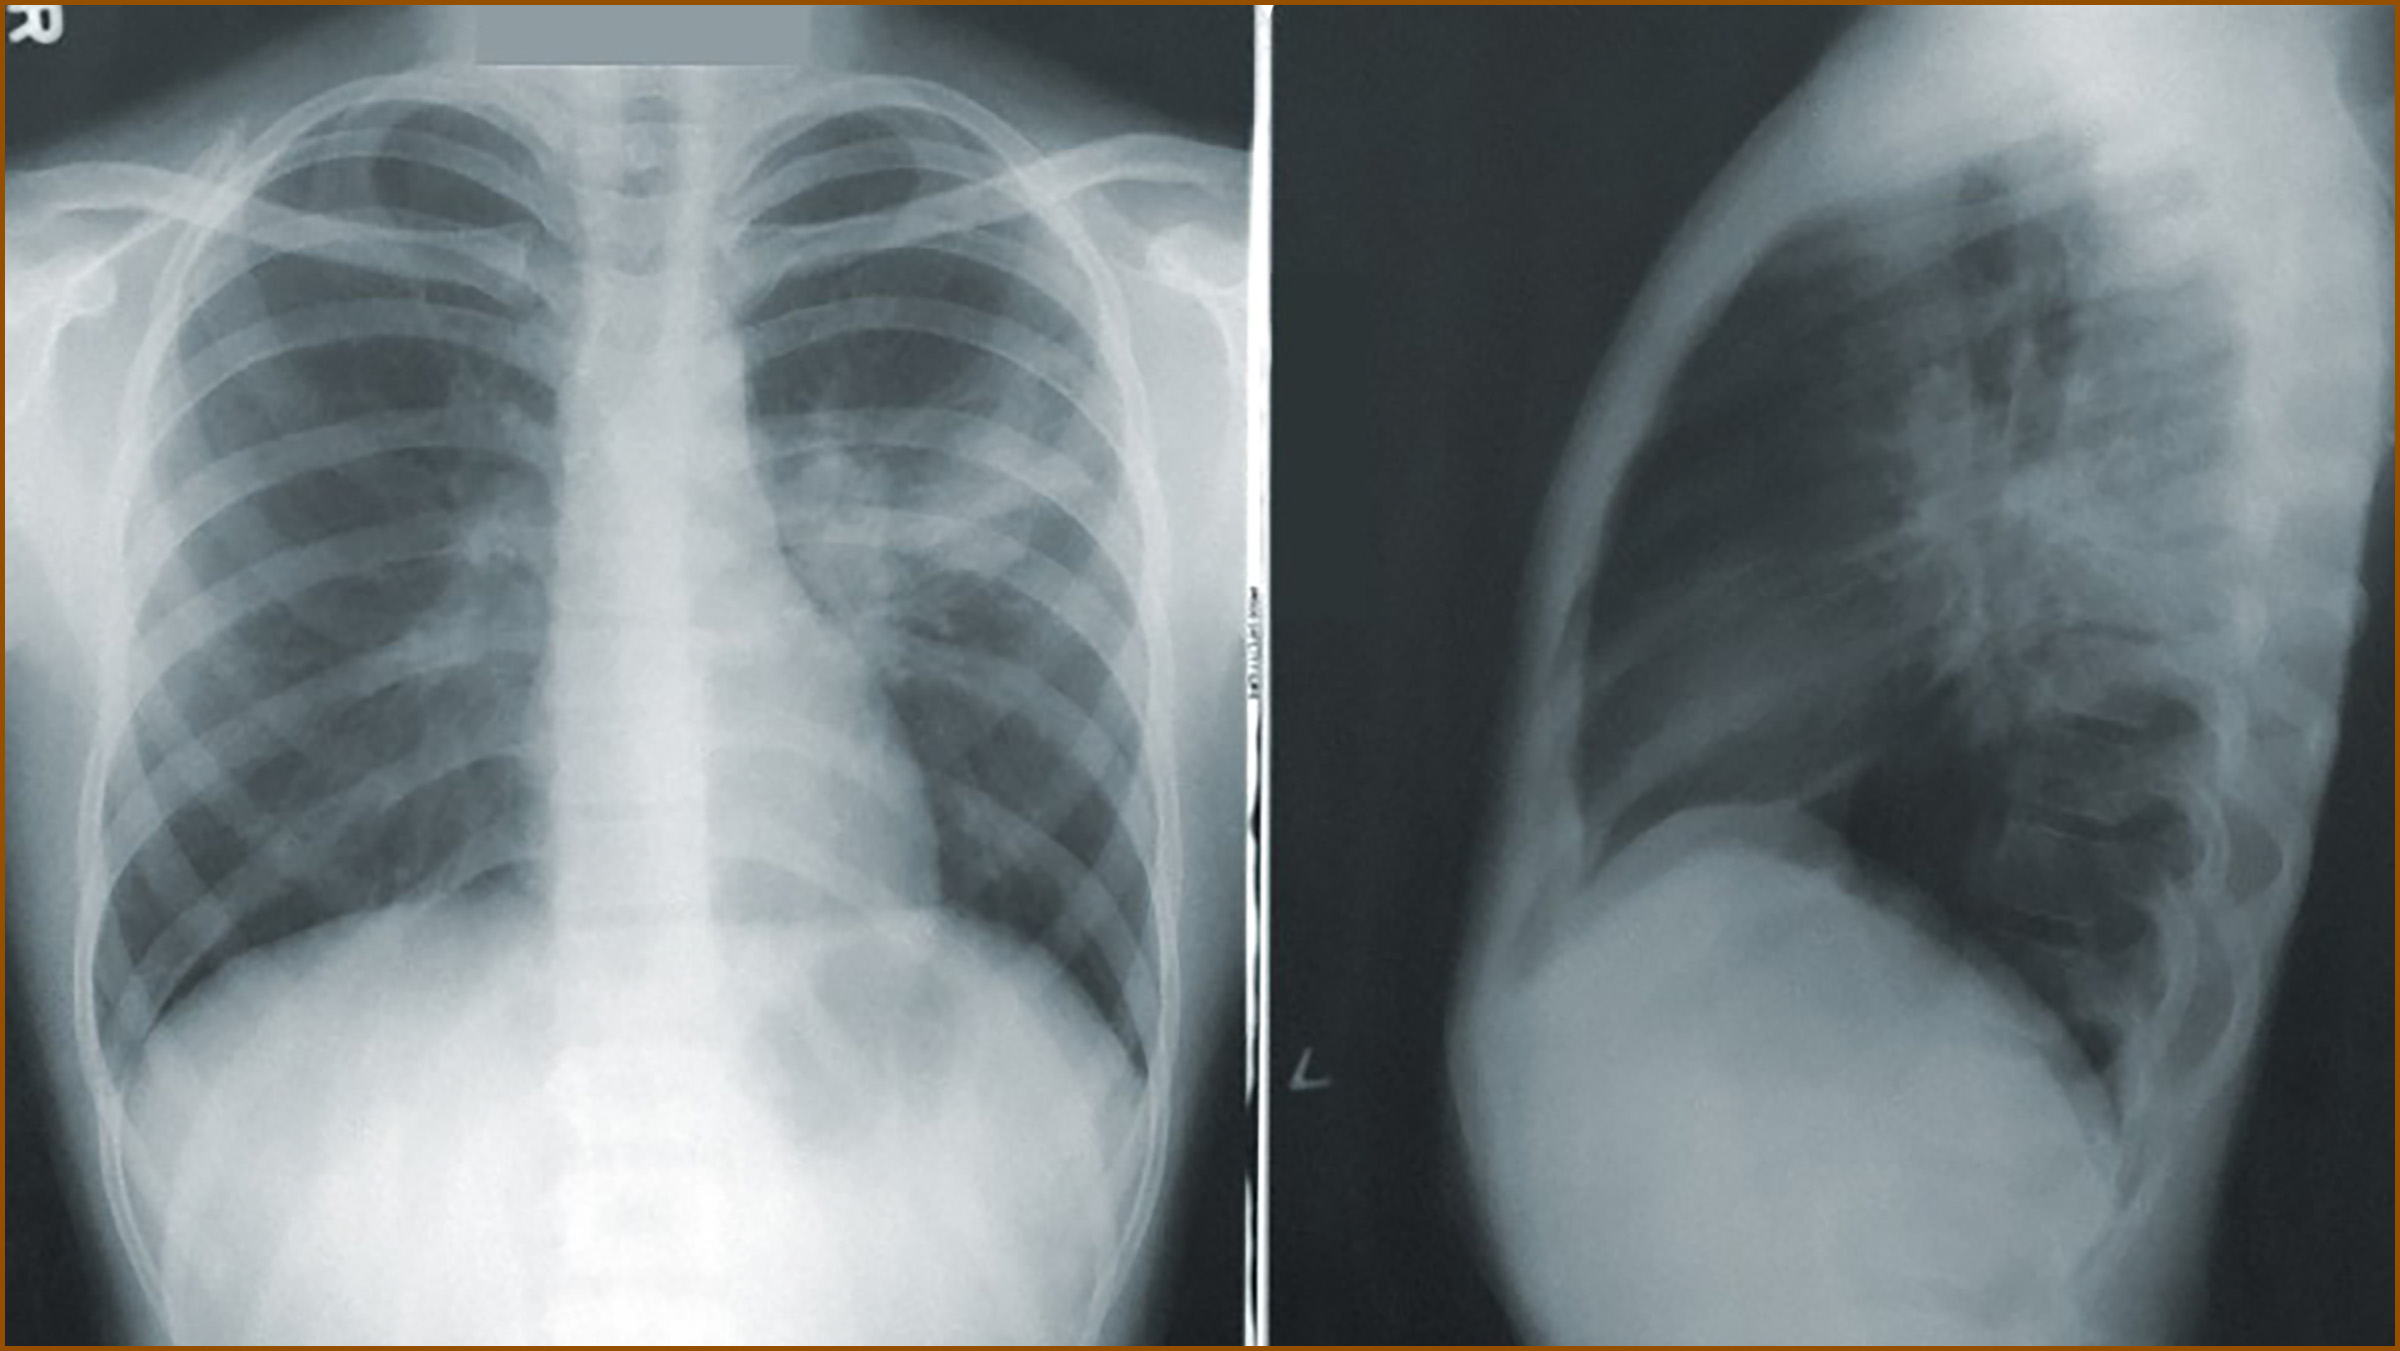

고립성 폐결절은 폐 내부에 생긴 구상 병변으로, 흉벽에 붙어있지 않고 폐 내부에 위치합니다. 1개의 종괴만 발견되기 때문에 고립성 폐결절이라고 부릅니다. 지름이 3cm 이하로 작은 크기를 가지며, 3cm를 넘어가면 조양이나 혹이라고 불립니다.

초기에는 무증상으로 알기 어려우나, 기침, 가래, 호흡 문제 등과 같은 폐질환과 유사한 증상이 나타날 수 있습니다. 폐결절은 악성 종양이 원인으로 밝혀진 성인의 약 35%에서 발견되며, 흡연자인 경우 폐결절 발생 확률이 더 높아집니다.

흉부 엑스레이 촬영 중 우연히 발견되는 경우가 많으며, 이는 초기 단계일 가능성이 높습니다. 어떤 병이든 초기 발견과 치료가 중요하므로 폐결절의 조기 발견과 치료가 중요합니다. 림프절이나 다른 장기로 전이될 수 있으며, 이 경우 예후가 좋지 않으며 나이가 많을수록 악성 종양으로 발전할 가능성이 큽니다.